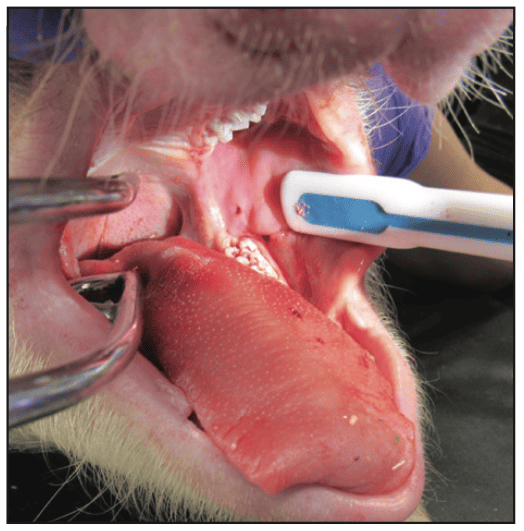

A predetermined microwave energy dose of one minute or less in duration would be delivered through the 3TBA handpiece using a proprietary microwave generator. After delivering the energy dose, the 3TBA handpiece is immediately removed and treatment is complete. The only post-op evidence of treatment in animals was a small puncture (Figure 3), which was not detectable 7 days following 3TBA treatment.

Figure 3. Immediate post-op view showing the small punc- ture made by the 3TBA micro-ablation handpiece in a porcine animal study.